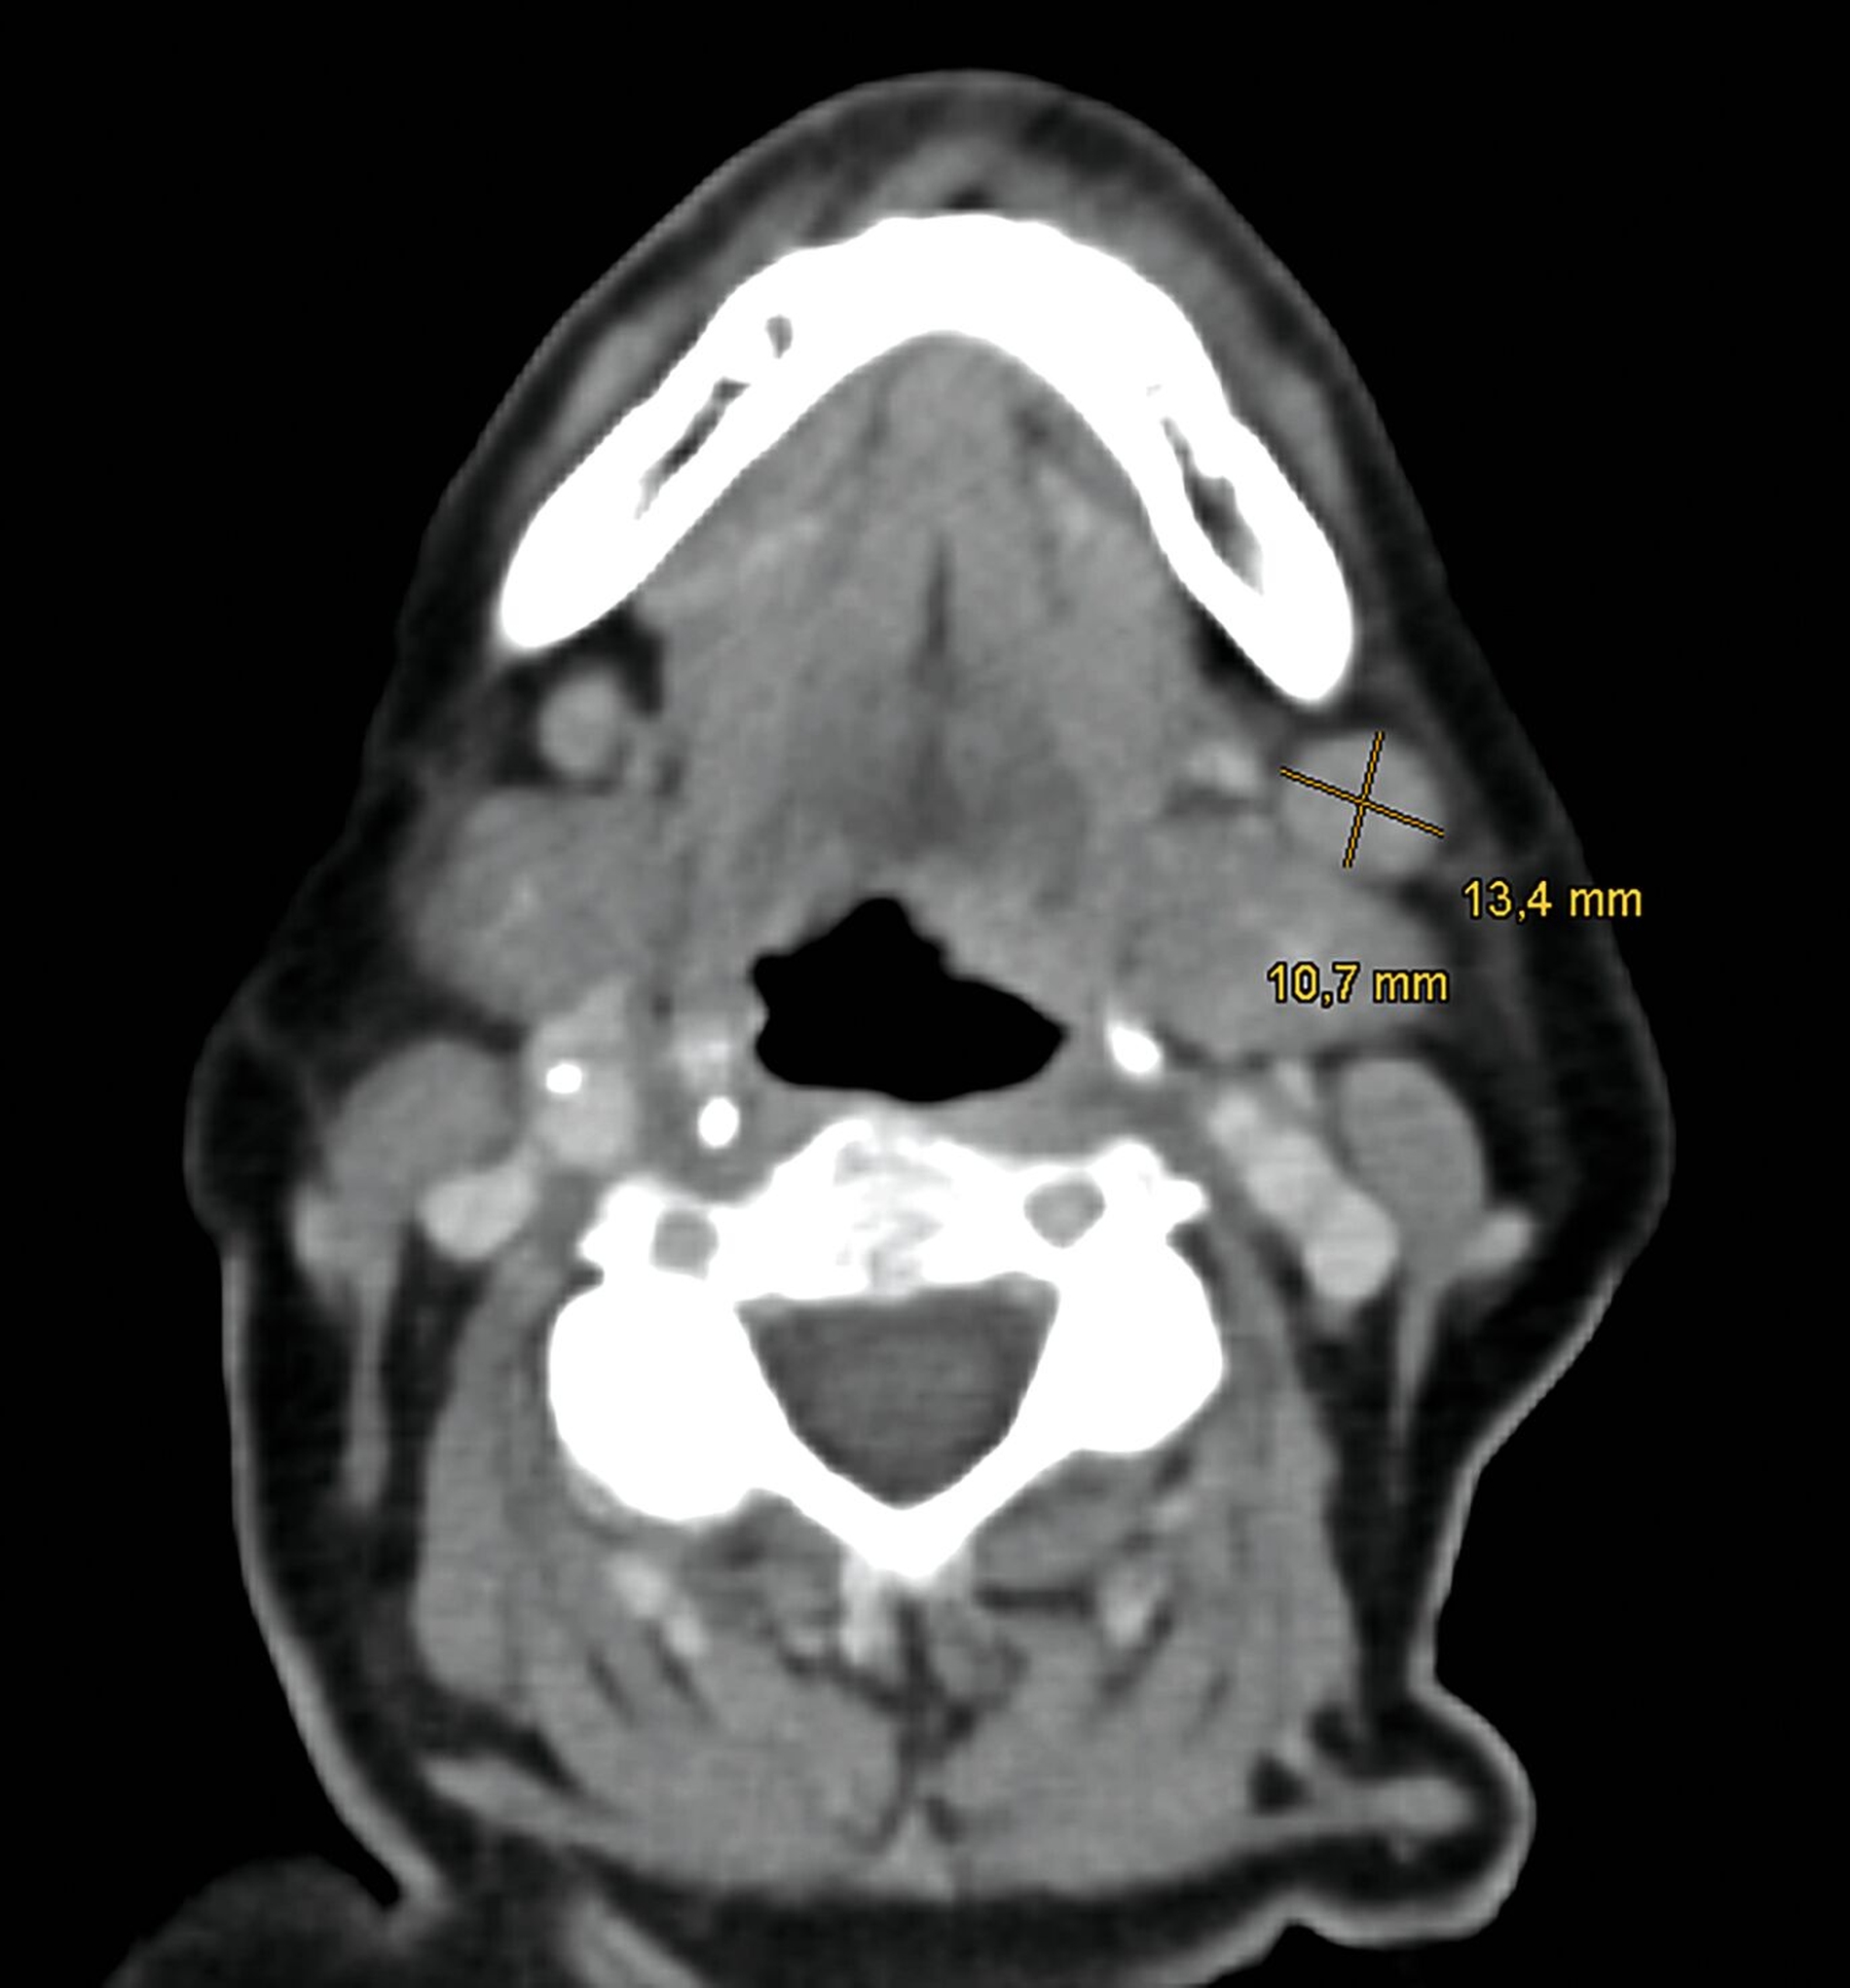

Es erfolgten eine Ausbreitungsdiagnostik mittels Ultraschall der zervikalen Lymphknoten, eine Computertomografie (CT) von Hals, Thorax und Abdomen sowie eine Magnetresonanztomografie (MRT) des Schädels. Radiologisch und sonografisch zeigten sich insbesondere in Level I A/B linksbetont suspekte Lymphknoten (Abbildung 3).